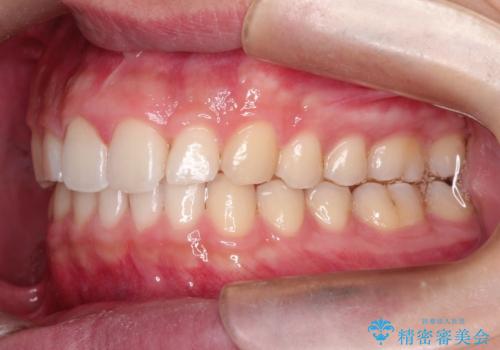

見た目、噛み合わせ及び、治療期間や施術内容に大変ご満足いただきました。